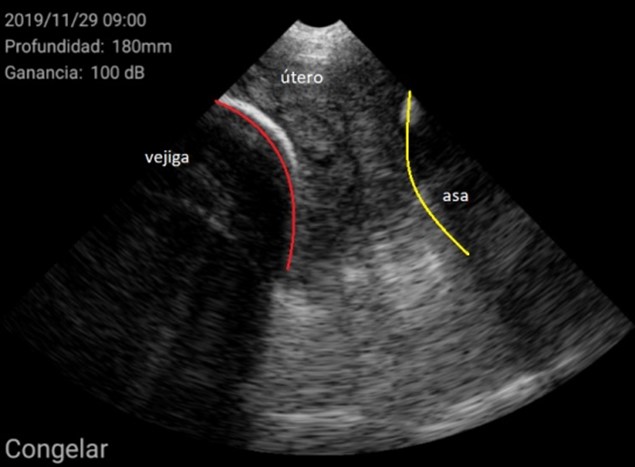

El diagnóstico se basó en la determinación del tamaño del útero y su posición en relación con otras estructuras como la vejiga urinaria o las asas intestinales. En general, se encuentra en posición ventral a la vejiga. Cuando el tamaño del útero es pequeño, ocupa muy poco espacio en la pantalla, de esta manera se considera una hembra impúber.

Por el contrario, úteros grandes, con cuernos uterinos identificables y que ocupan gran superficie de la pantalla se consideran como hembra púber.

Imágenes de cerdas Púberes con el ecógrafo W3 de Kubus